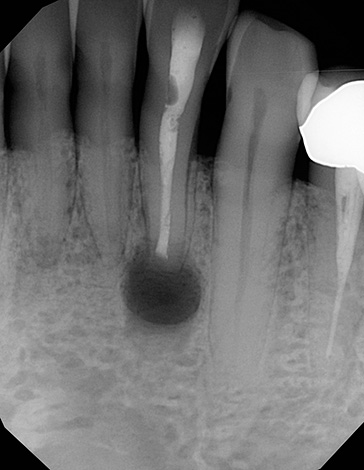

A foto abaixo mostra um exemplo de um dente da frente quebrado a ser removido: